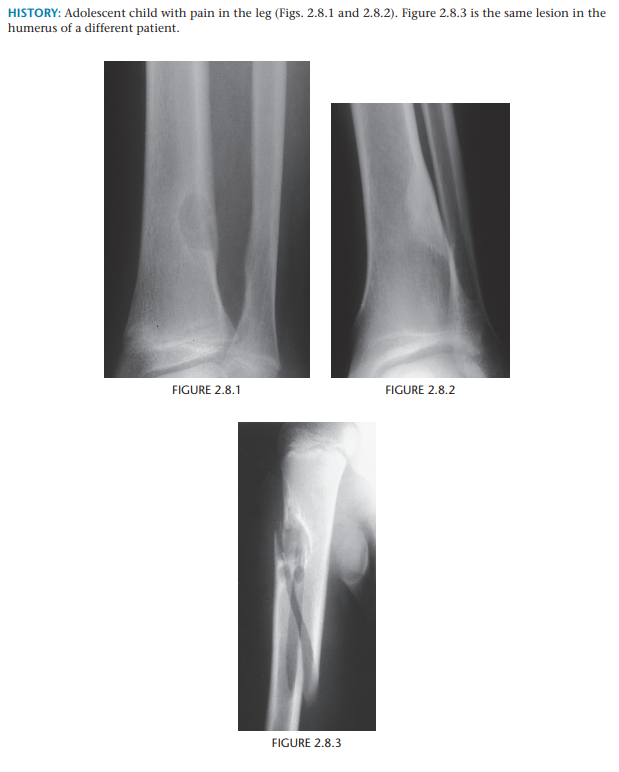

Unicameral bone cyst

Unicameral bone cysts are most common in the proximal humerus and femur.

The fallen-fragment sign confirms the cystic nature of this lesion.